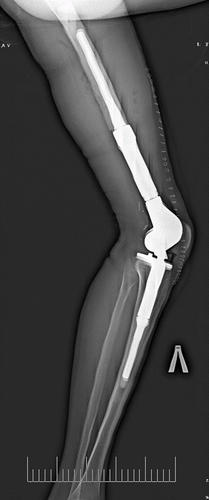

Рентген нижних конечностей: Подробный анализ